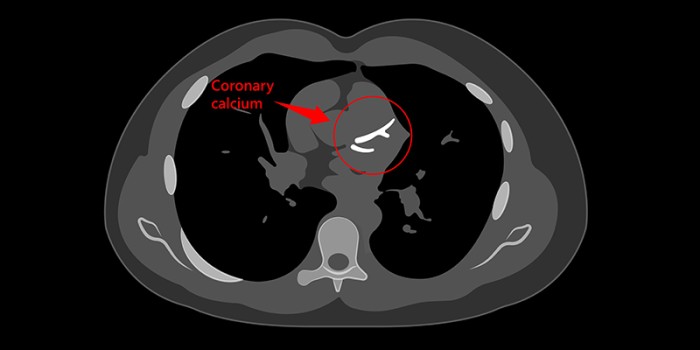

Hartkatheterisaties spelen een steeds kleinere rol bij de diagnostiek van stabiele angina pectoris (SAP), omdat niet-invasieve beeldvorming in veel gevallen minstens gelijkwaardig is.1 Daarnaast is de fietsergometrie onvoldoende accuraat gebleken om kransslagaderlijden aan te tonen en uit te sluiten. De NHG-Standaard Stabiele angina pectoris adviseert dan ook elke patiënt met (a)typische klachten van SAP voor diagnostiek naar de cardioloog te verwijzen.2 Huisartsen kunnen de niet-invasieve scans immers niet zelfstandig aanvragen. Vooral bij atypische SAP en aspecifieke thoracale klachten die mogelijk toch op kransslagaderlijden wijzen, zijn huisartsen en patiënten gebaat bij een snelle triage en alleen op indicatie doorverwijzing naar de cardioloog. Een CT-scan met coronaire kalkscoremeting, aangevraagd door de huisarts, kan hierbij helpen.3

Met het CONCRETE-onderzoek willen we nagaan of een dergelijk zorgpad met CT-kalkscoremeting via de huisarts patiëntvriendelijk en goedkoop in te richten is. De interventiegroep omvat patiënten met atypische SAP en patiënten met atypische thoracale klachten bij wie de huisarts tóch kransslagaderlijden vermoedt. De huisarts laat bij deze patiënten zelfstandig een CT-kalkscore bepalen, nadat ze alvast met medicatie zijn gestart. Bij een lage kalkscore verwerpt de huisarts de diagnose kransslagaderlijden en stopt de medicatie. Bij een matige kalkscore optimaliseert de huisarts het CVRM en bij een hoge score krijgt de patiënt een verwijzing naar de cardioloog. In de controlegroep levert de huisarts reguliere zorg en krijgt iedere patiënt dus een verwijzing naar de cardioloog. We beogen in beide groepen 800 patiënten te includeren.4